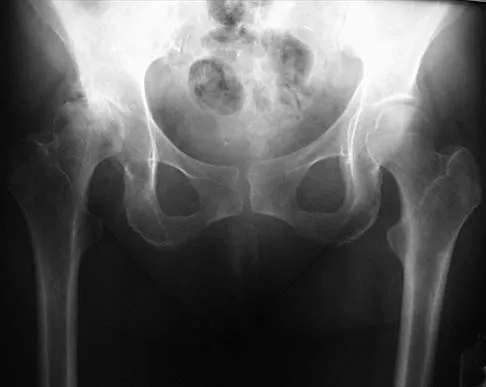

A 21-year-old collegiate female cross-country athlete reports right hip pain that begins about 12 miles into a run, followed by pain resolution when she discontinues running. However, each time she tries to resume a running program, she experiences recurrence of pain deep in the anterior groin. A plain radiograph and MRI scan are shown in Figures 8a and 8b. Management should consist of

Explanation

The history is consistent with a stress fracture. Findings on the plain radiograph are marginal, but the MRI scan shows evidence of stress reaction in the medial neck of the femur (compression side). A lesion on the compression side is not normally at risk for displacement and usually can be managed nonsurgically. A bone scan would further identify the lesion but is not necessary. A skeletal survey and chest radiograph are used in staging a tumor. Radioisotope injection and guided biopsy are sometimes used for osteoid osteomas. Boden BP, Osbahr DC: High-risk stress fractures: Evaluation and treatment. J Am Acad Orthop Surg 2000;8:344-353.